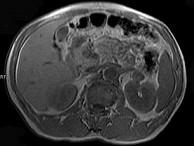

问题 男,52岁,下肢无力伴多饮多尿2年余,实验室检查:低血钾,血醛固酮水平及24小时尿醛固酮定量超过正常值,MRI检查如图所示,应诊断为()

选项 A.左肾上腺囊肿 B.左肾上腺腺瘤 C.左肾上腺嗜铬细胞瘤 D.左肾上腺髓脂瘤 E.左肾上腺转移瘤

答案 B